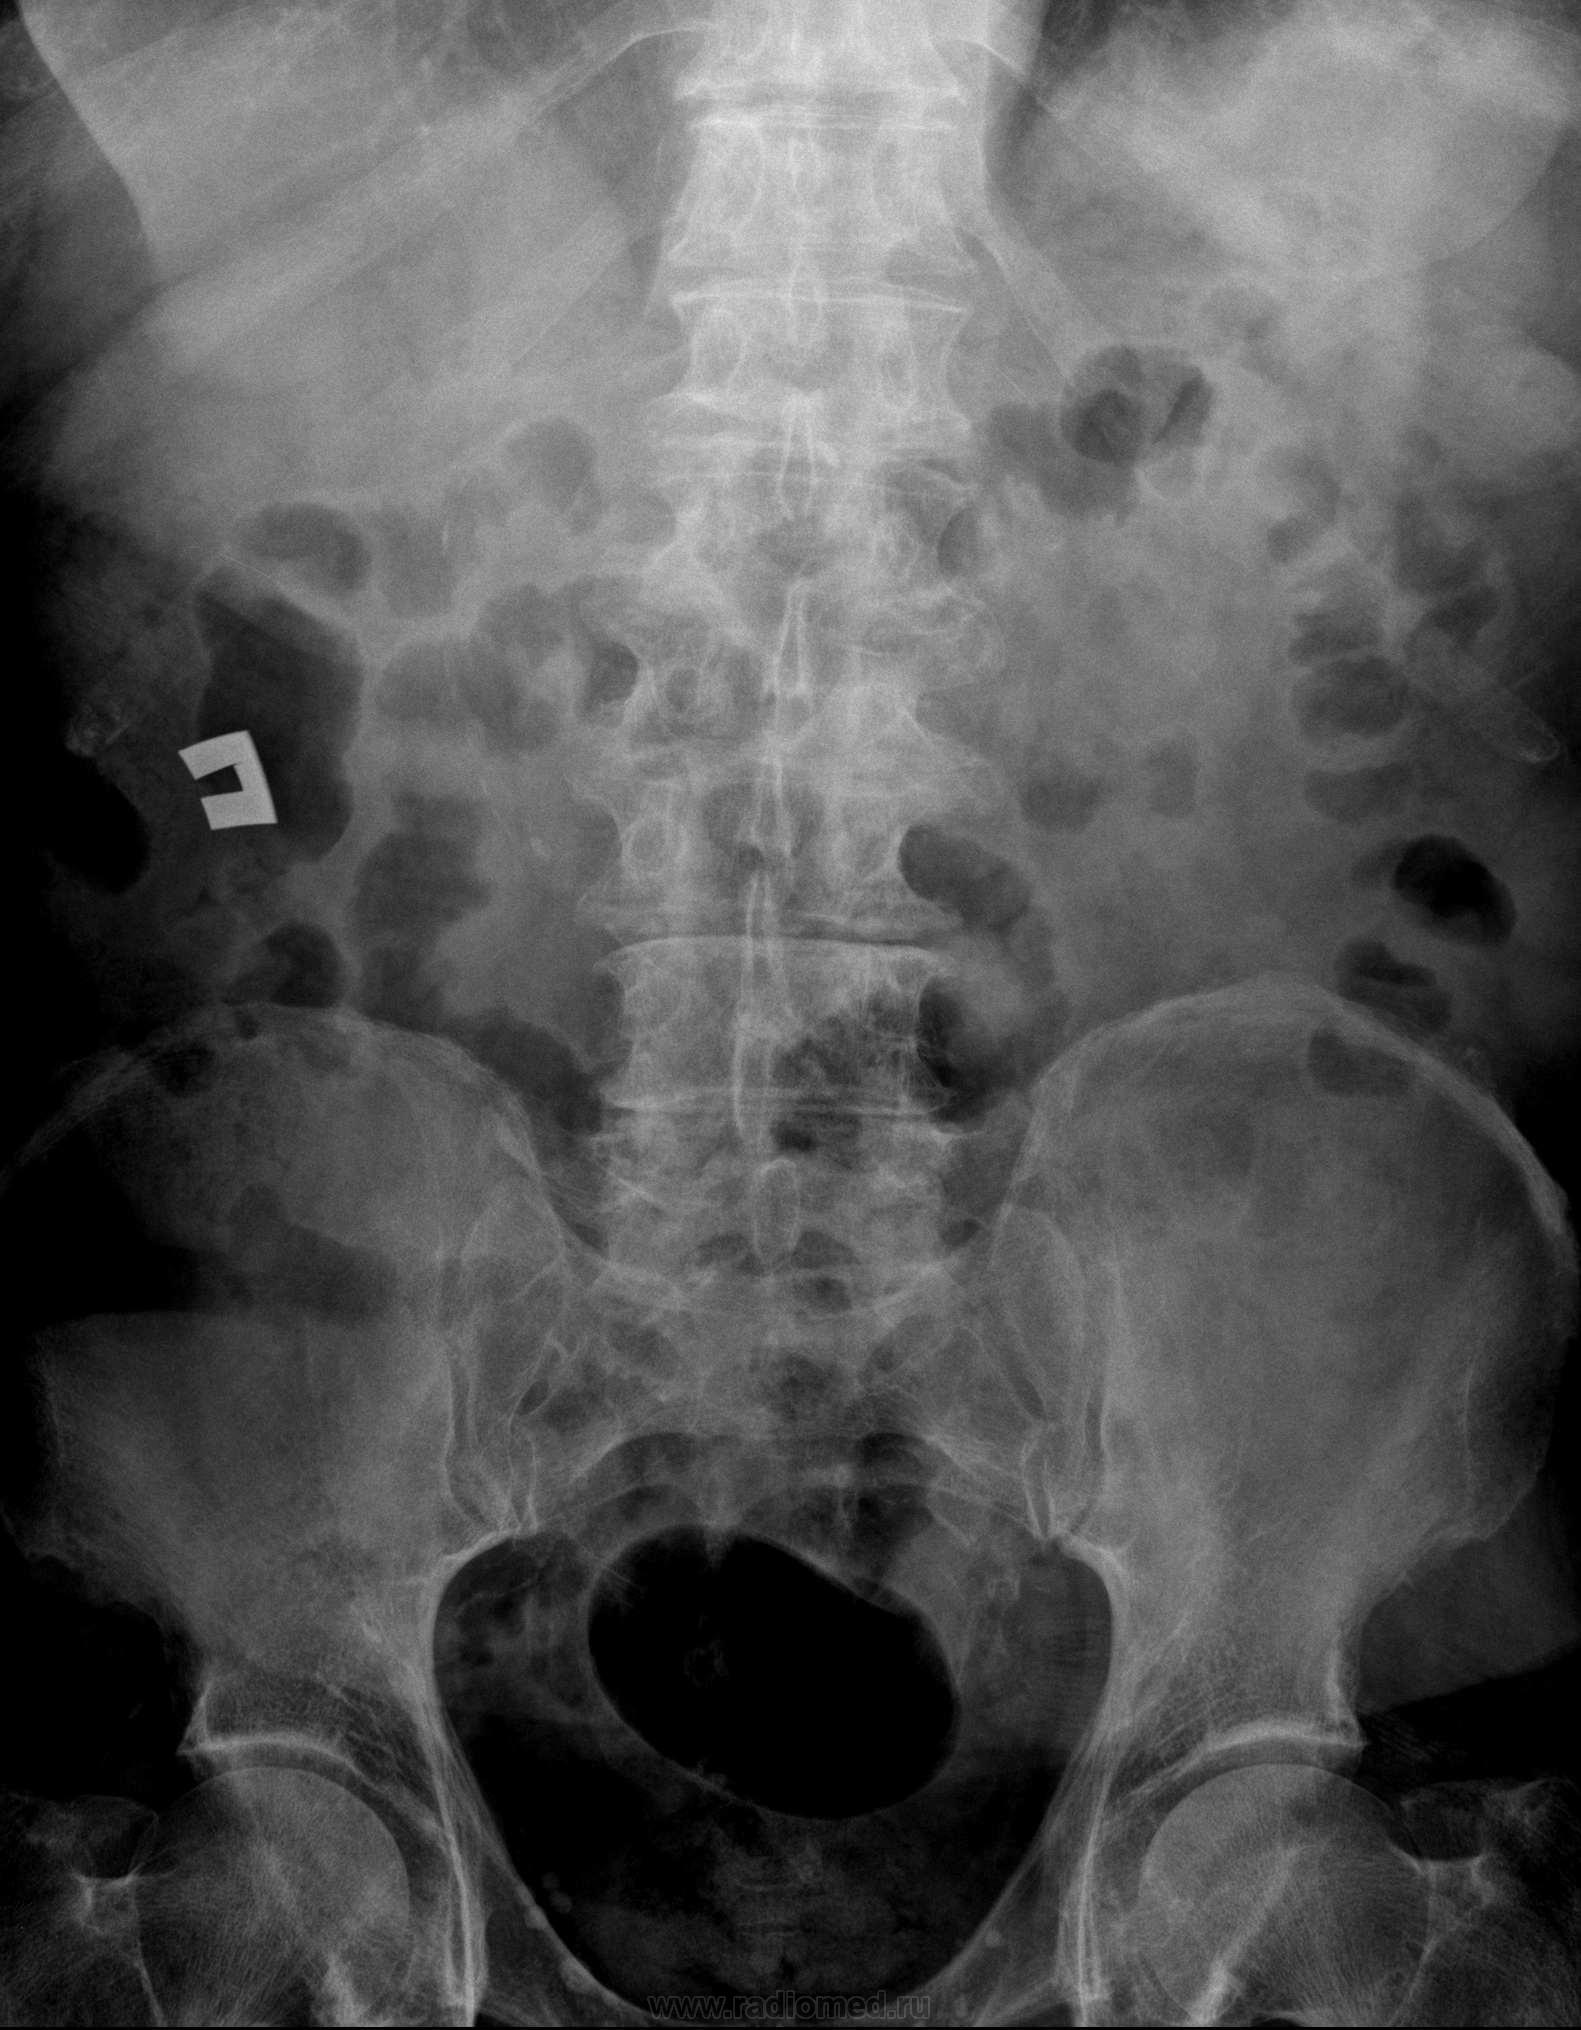

С какой стороны колика-то? Если справа, то там есть тень, "подозрительная на конкремент" (красная стрелка). Да смущают ещё тенёчки, отмеченные жёлтым.

Возможно, я бы придрался к тени "характера конкремента", возможно, желтая стрелка, по более пристально, я - бы рассматривал "цепочку" отмеченную красными стрелками.

А если раскрутить эти "цепочки", что получиться? Колика якобы правосторонняя.

Да, это может быть что угодно, в том числе и расслаивающаяся аневризма.

Похоже на обызвествление края аневризмы!

Вот мне тоже показалось, что "цепочка" -- но если рассматривать её так широко, как Вы отметили (хотя лично мне две последние, нижние кажутся сомнительными), то к мочевыводящим путям её никак "не пристегнешь". Обызвествление стенки чего-то полого?

Аневризма абдоминального отдела аорты с прорывом забрюшинное пространство и образованием гематомы, от подпеченочного пространства до малого таза.